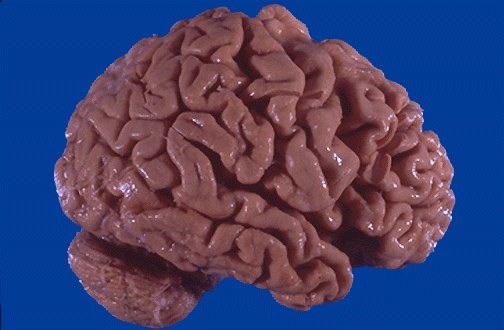

Alzheimer's disease leads to cerebral atrophy. Shown here is the external surface of the brain with widened sulci and narrowed gyri, mostly over the frontal and parietal regions, gross.